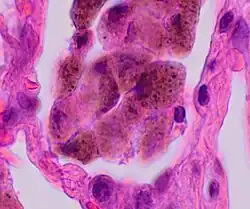

Comparison of pigmented pulmonary macrophages

| Disease | Macrophage name | Macrophage pigment appearance (HE stain) | Usual macrophage location | Associated medical history | Image | Image comment |

|---|---|---|---|---|---|---|

| Anthracosis | Black-brown granules | Interstitium (perivascular) |

|

Black arrow shows interstitial anthracotic pigment. Nearby macrophages (white arrow) can be presumed to contain anthracotic pigment. | ||

| Respiratory bronchiolitis | "Smoker’s macrophages" | Yellow to light brown and finely granular[4] | Airways (especially respiratory bronchioles) | Tobacco smoking |

Smoker's macrophage in center |